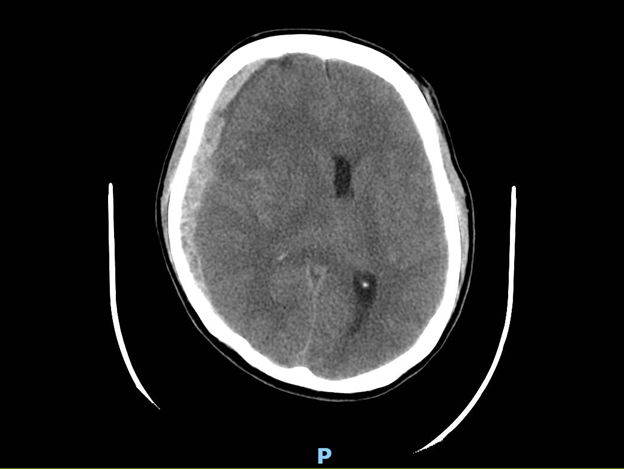

Bệnh nhân nam N.V.H 39 tuổi bị tai nạn giao thông hôn mê được đưa vào viện trong tình trạng: Bệnh nhân mê. Vết thương trán trái đang chảy máu, đồng tử 2 bên 3mm phản xạ ánh sáng yếu (Tình trạng chèn ép não nặng). Tình trạng nguy kịch đe dọa tính mạng. Bệnh nhân được tiến hành xử lý cấp cứu và hội chẩn khẩn Ngoại Thần Kinh có chỉ định mổ cấp cứu mở sọ giải ép lấy máu tụ bán cầu phải với chẩn đoán: Máu tụ dưới màng cứng cấp bán cầu phải.

Hình 1: Phim CT scan sọ não trước mổ (lớp máu tụ dưới màng cứng đè ép não, đẩy lệch đường giữa)